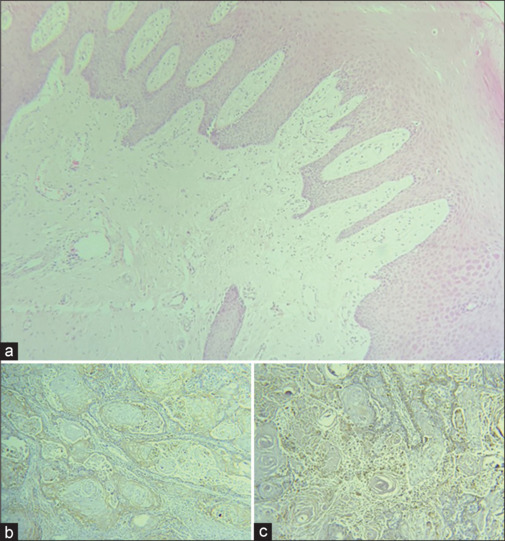

Background: Over the past 5 years, the use of immune checkpoint inhibitors in the treatment of head-and-neck squamous cell carcinoma (HNSCC) has increased. Both programmed death-ligand 1 (PD-L1) and cluster of differentiation 68 (CD68) are overexpressed in various carcinomas. Consequently, evaluating the expression of CD68 and PD-L1 in HNSCC lesions may lead to detecting a possible marker for HNSCC. This study aimed to evaluate the expression of PDL1 and CD68 markers in a patient with oral squamous cell carcinoma (OSCC) and examine its relationship with depth of invasion (DOI) and immunofluorescence (IF) through immunohistochemistry.

Materials and methods: This cross-sectional study was conducted in the School of Dentistry, Mashhad University of Medical Sciences, Mashhad, Iran, Department of Oral and Maxillofacial Pathology. Thirty-four paraffin blocks and demographic information of 15 female and 19 male OSCC patients were collected. Following sample preparations, immunohistochemical staining was performed. Subsequently, each tissue section was analyzed for tumor-infiltrating lymphocytes by CD68 marker and PD-L1 expression. Data analysis was conducted using SPSS software (version 25). Chi-square, Shapiro-Wilk, and independent t-analytical tests were employed for statistical assessments. P < 0.05 was remarked as statistically significant.

Results: CD68 and PDL1 expression in the squamous cell carcinoma (SCC) group was higher than the control group (P < 0.001). There was an increasing expression of PDL1 and CD68 as the grade of the disease progressed (P < 0.001 for each), as well as an increasing expression of IF and DOI.

Conclusion: The expression levels of CD68 and PDL1 were elevated in SCC tissues in comparison to the unaffected, healthy parts of the tissue section.